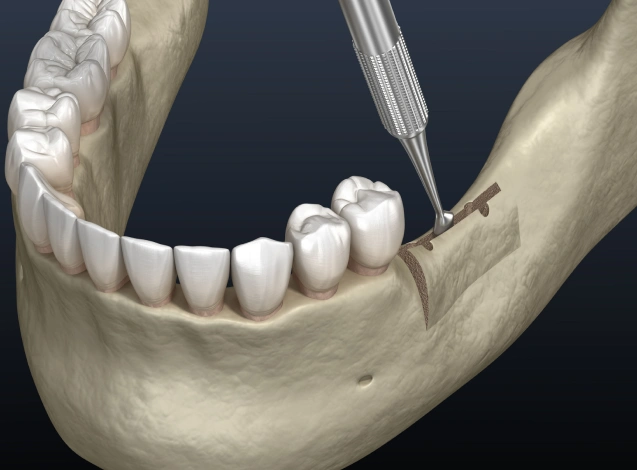

Ridge Augmentation: Restoring Jawbone Height and Width

When teeth are missing for an extended period or due to trauma, the jawbone can shrink and lose its natural shape. Ridge augmentation uses grafting material to rebuild the height and width of the bone and restore the natural contour of both the jaw and the gums. This procedure not only creates a stable foundation for dental implants but also improves aesthetic outcomes, ensuring that your new smile looks as natural as it feels.

After grafting material is carefully placed, the site is sutured and allowed to heal. Once the bone integrates, it becomes strong enough to support implant placement, ensuring long-term success and stability for your implants.

Socket Preservation: Preventing Bone Loss and Preparing for Implants

After a tooth is removed, the jawbone in that area naturally begins to shrink. To preserve the natural contours of your jaw and create a strong foundation for future dental implants, we perform socket preservation at Anchor Dental Implant Center. This specialized bone grafting procedure helps prevent bone loss and preserves bone volume to ensure a secure and stable implant placement in the future.

During the procedure, the tooth socket is thoroughly cleaned, and a biocompatible grafting material is placed. This material stimulates your body’s natural bone regeneration process, allowing the area to heal while gradually rebuilding the necessary bone structure. Once the graft has integrated, it prepares the site for the successful placement of a dental implant.